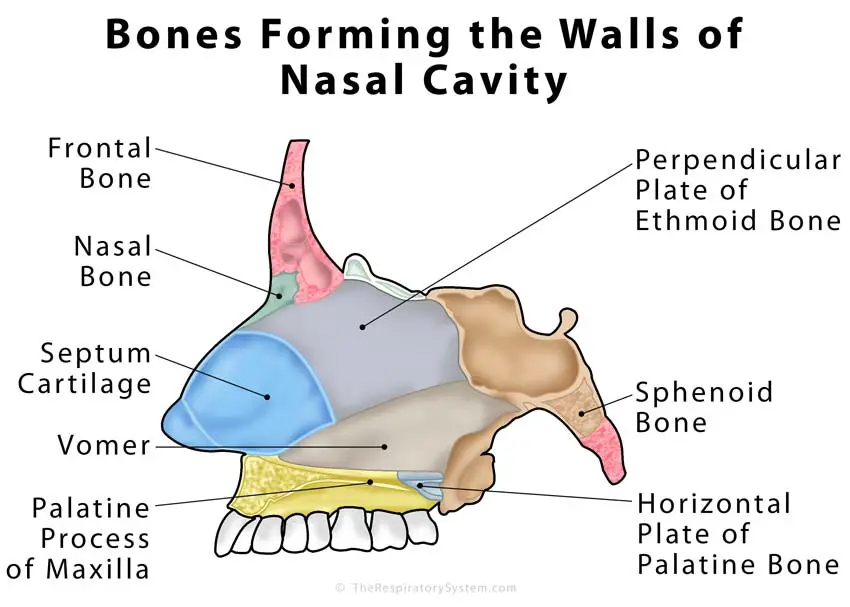

In bones behind your nose are your sphenoid sinuses. Anatomy of the nasal cavity. This region is divided into a labyrinth of slit like passages by multiple bony proturbances that fill the nose and act as shelves.

The external nose consists of paired nasal bones and upper and lower lateral cartilages. The nasal cavity refers to the interior of the nose. The nasal cavity is the most superior part of the respiratory tract.